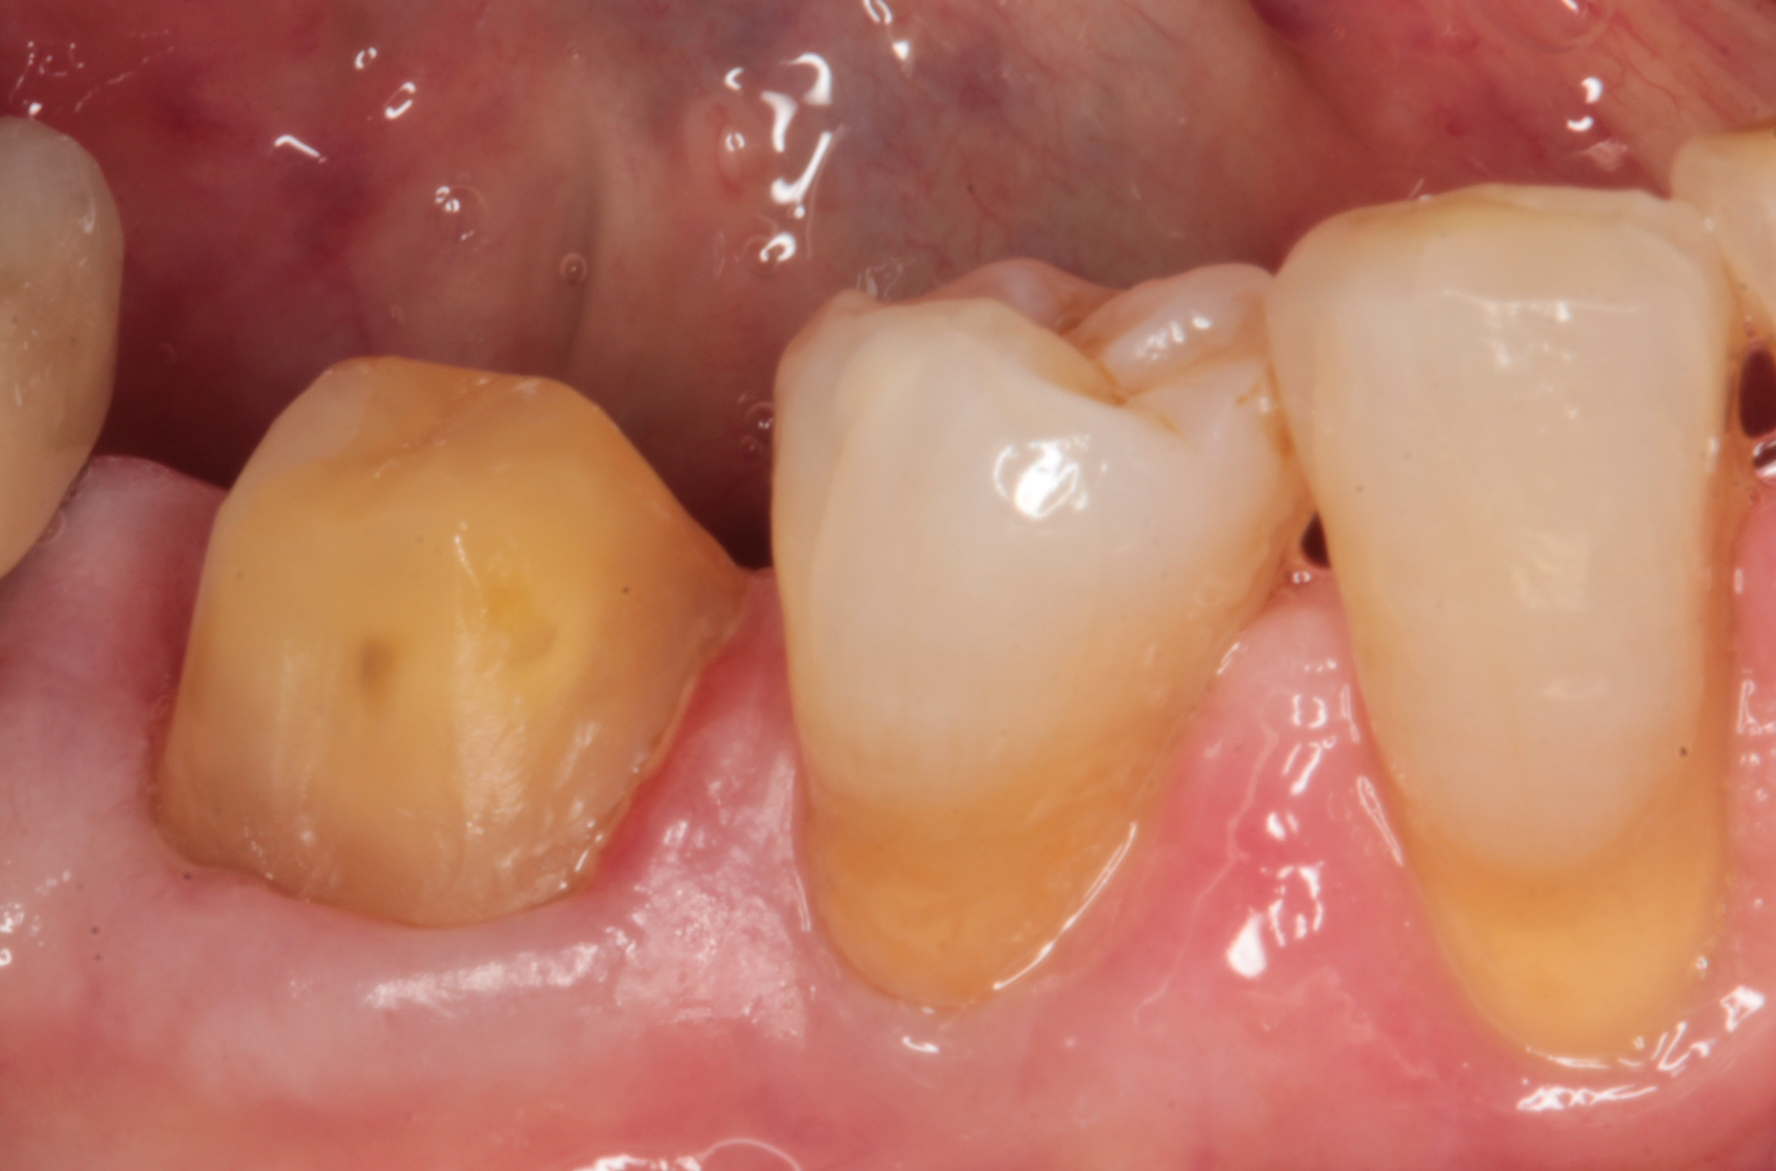

Figures 1 and 2 show the facial and occlusal views of a madibular molar that I prepared for a full crown.

Fig. 1 Fig. 2 Fig. 3